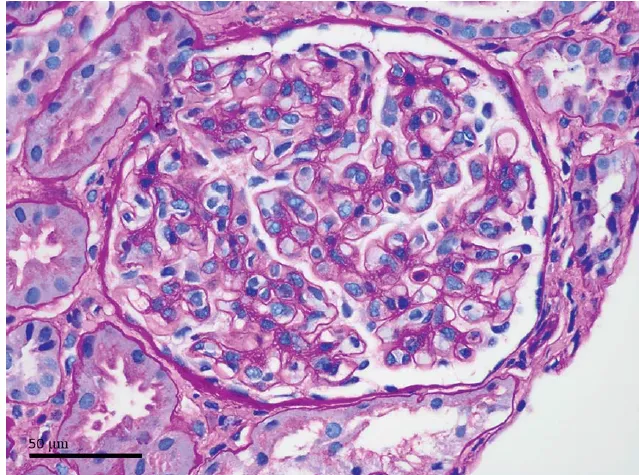

Diante da piora das escórias o paciente iniciou hemodiálise, sendo iniciado também tratamento corticosteroide em alta dose (prednisona 80 mg/dia) e anticoagulação com heparina. Foi realizado biópsia renal no quinto dia de internação.

A biópsia renal foi compatível com nefropatia membranosa, além disso, foi identificado marcação na membrana basal glomerular para NELL1 (imuno-histoquímica para NELL1, 400×).